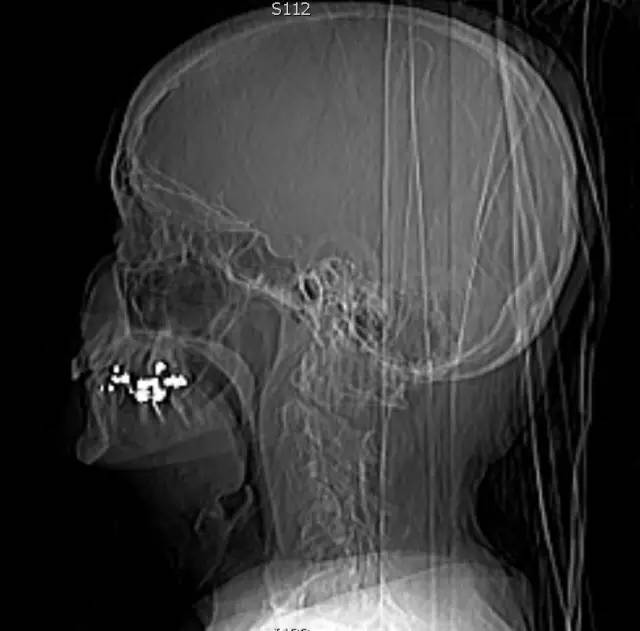

【病例】II型齿状突骨折1例

【病史】女性,急诊。

【影像学表现】

急性横行齿突骨折,C2椎体与齿突尖分离约7mm。齿突尖仍与C1前弓正常排列。

【诊断】II型齿突骨折

Type 2 odontoidprocess fracture